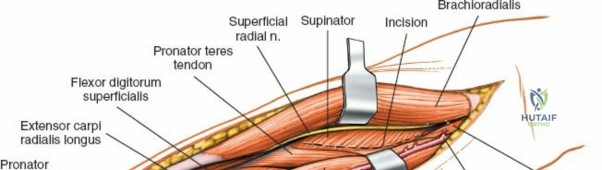

Superficial Surgical Dissection and Internervous Plane

Incise the deep fascia of the forearm in line with the skin incision. The initial goal is to identify the medial border of the brachioradialis as it courses down the forearm. It is a common pitfall to search for this border too far laterally. At the level of the elbow, the brachioradialis is expansive and extends almost halfway across the anterior forearm. It is surprisingly easy to mistake the plane between the brachioradialis and the extensor carpi radialis longus for the correct intermuscular plane.

To confirm the correct plane, look for the superficial branch of the radial nerve. This sensory nerve runs on the undersurface of the brachioradialis muscle. Once the true medial edge of the brachioradialis is found, develop the plane between it and the pronator teres (proximally) or the flexor carpi radialis (distally). Retract the brachioradialis laterally, taking care to keep the superficial radial nerve attached to its undersurface to protect it from traction injury.

Exposing the proximal third of the radius requires extreme vigilance due to the proximity of the posterior interosseous nerve. The key anatomical landmark here is the insertion of the biceps tendon. Follow the biceps tendon distally to its insertion on the bicipital tuberosity of the radius. A small bursa lies just lateral to the tendon; incise this bursa to gain initial access to the proximal radial shaft. Because the radial artery lies superficial and medial to the tendon at this level, all deep dissection must remain strictly lateral to the biceps tendon.

The proximal radius is draped by the supinator muscle. The PIN passes directly through the belly of the supinator. To protect the nerve, the forearm must be fully supinated. Supination dynamically rotates the radius, carrying the insertion of the supinator anteriorly and simultaneously displacing the PIN laterally and posteriorly, safely away from the surgical field.

With the forearm fully supinated, identify the broad insertion of the supinator on the anterior aspect of the radius. Incise the supinator directly along the line of its insertion onto the bone. It is critical to detach the muscle by dividing its insertion sharply at the bone, rather than splitting the muscle belly, which would risk cutting the PIN.

Proceed with strict subperiosteal dissection, elevating the supinator laterally off the bone. This is one of the rare instances in orthopedic surgery where the safety gained by staying in a subperiosteal plane completely outweighs the theoretical vascular damage to the bone caused by periosteal stripping. The elevated supinator muscle belly now acts as a protective cushion for the PIN.